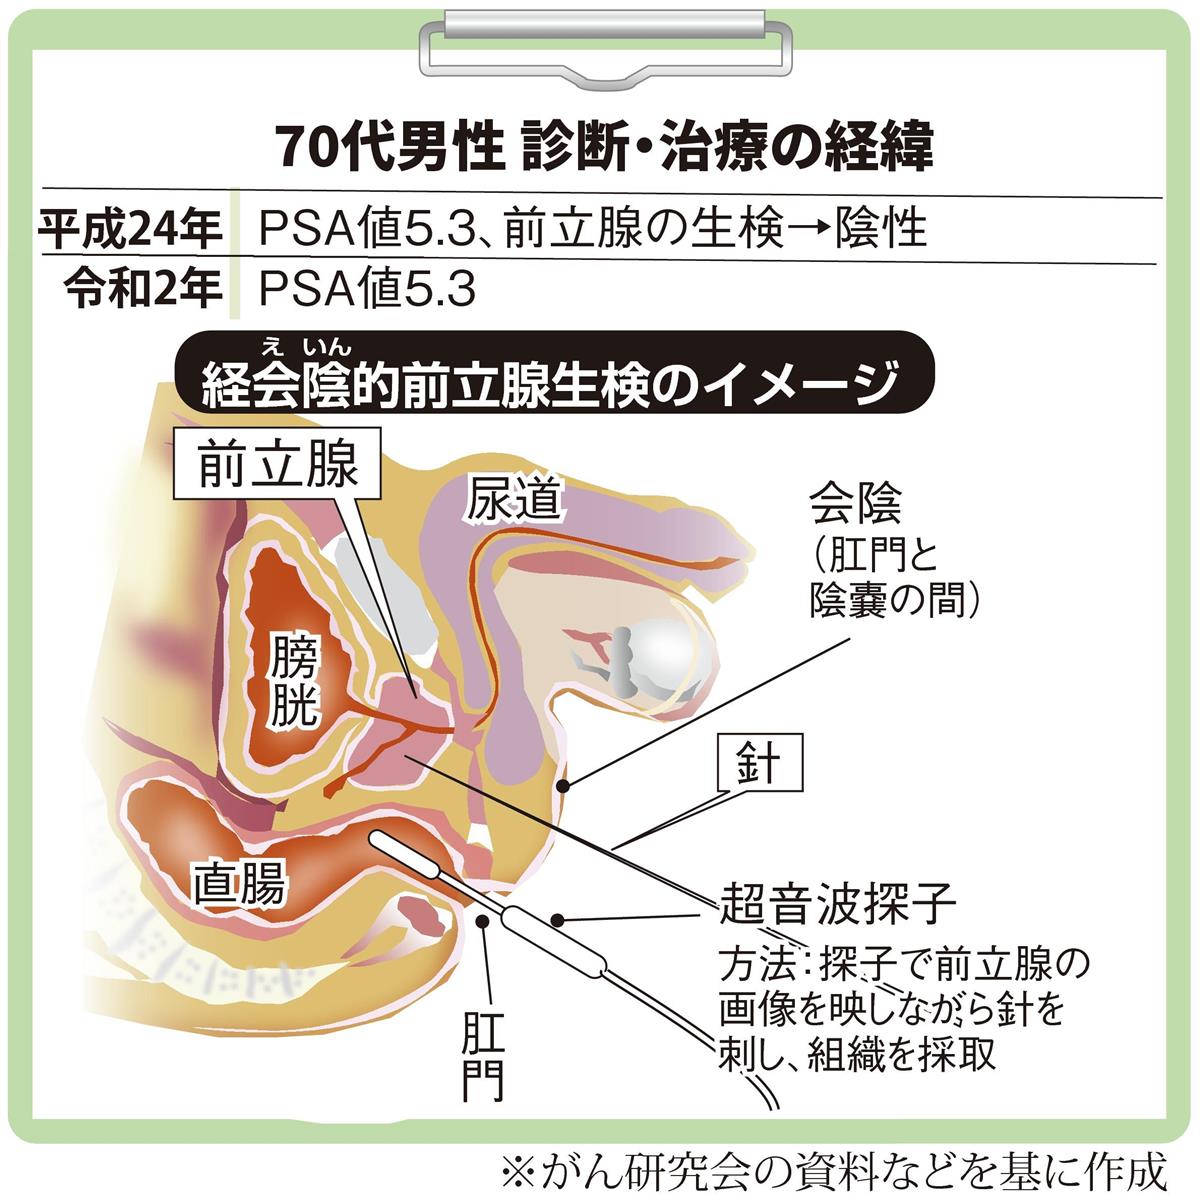

がん電話相談から 前立腺がんグレーゾーン 次の検査は 産経ニュース